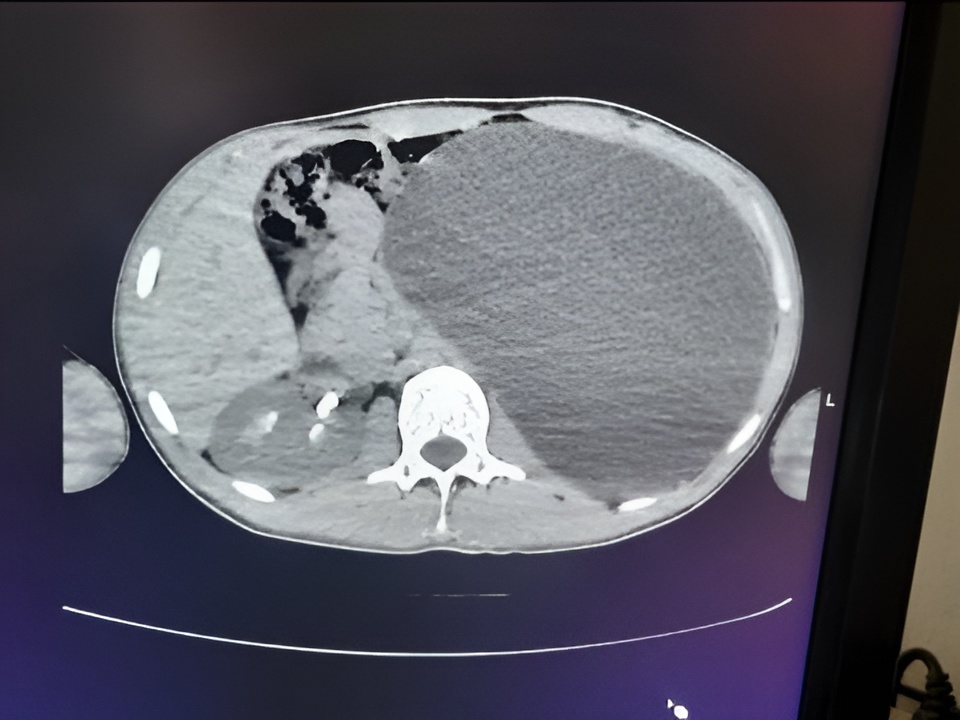

Юноша чувствовал себя абсолютно здоровым и никогда не предъявлял жалоб на мочевыделительную систему. Однако диагностика выявила страшную патологию: почка пациента достигла размеров пятилитровой бутылки и занимала практически всю брюшную полость, сдавливая соседние органы.

«Это была настоящая бомба замедленного действия, — подчеркнули в пресс-службе Детской городской клинической больницы № 1. — Любая травма, неосторожный удар в живот — и орган мог разорваться, что привело бы к внутреннему кровотечению и гибели пациента».